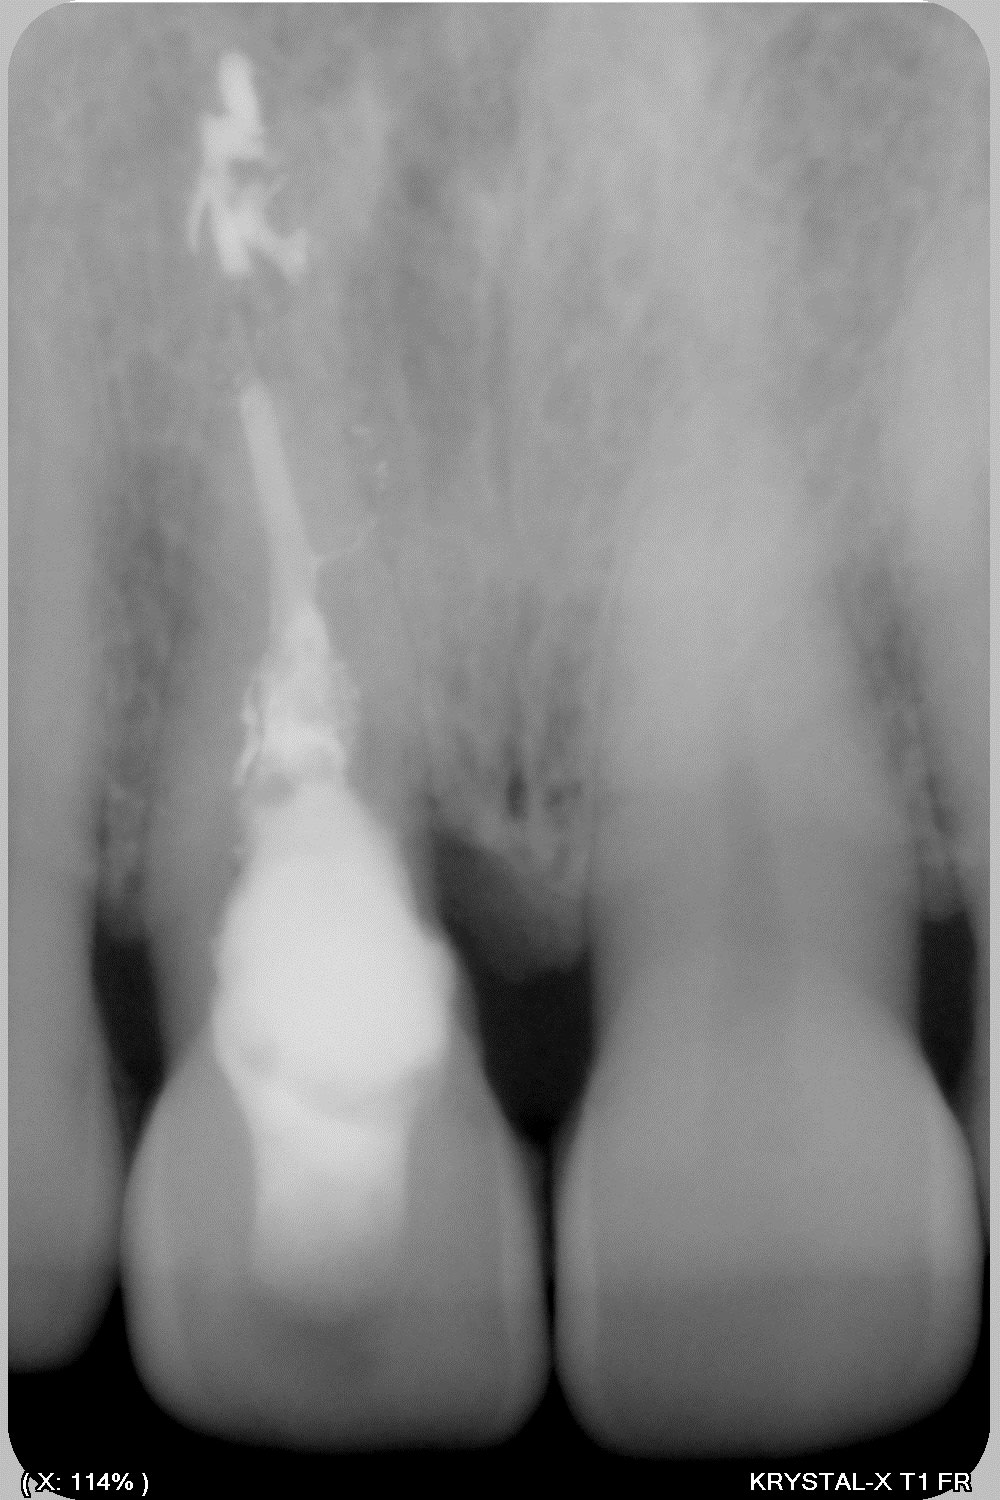

nettoyage et obturation

je n'avais encore pas de biodentine donc le produit c'est du Vitalos (utilisé en implanto, bitube qui durcissait) qui n'est plus commercialisé depuis 8 ans je crois donc la radio initiale ne date pas de plus de 10 ans mais ça fera 10 ans dans 485 jours... intervention 07/2011) la dernière radio est de la semaine dernière... je n'avais pas revu la patient (qui a donc 48 ans maintenant) depuis 7 ans et honnêtement je pensais qu'elle avait migré ailleurs, et bien non comme tout allait bien, donc pas de contrôle.

le Vitalos n’était pas destiné à cet usage mais j'ai fait une transposition des résultats que j'avais dans d'autres usage.

L’avantage c'est qu'il collait aux parois séchées à la compresse et était biocompatible mais je ne désirait que l'os prenne sa place

Le seul petit défaut sur la dernière radio, c’est la perte osseuse en mésial, par contre la gencive à toujours la bonne hauteur (je n’avais pas fait de décharge latérale, papilles en ½ épaisseur…) et un aspect sympa, dent solide patiente avec un joli sourire